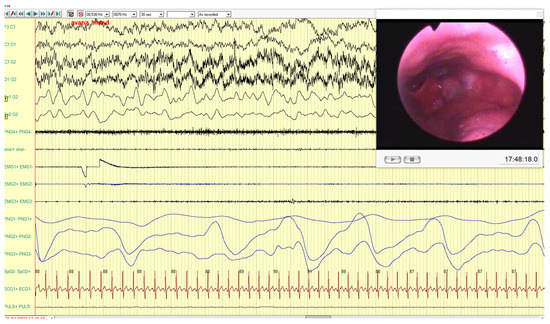

Similarly, for the male patient, results recorded were better with the fork advancement (Figure 8 and Figure 9).

Figure 8. In this frame, it is possible to observe the persistence of obstructive apnea with desaturation (85–89% range) during the bimanual mandibular advancement maneuver. Furthermore, the persistence of muscle activities on intercostal muscle (EMG3) and on masseter muscles (EMG1, EMG2) is noticeable.

Figure 9. In this frame, the immediate improvement effect on all respiratory parameters with normal saturation values during the mandibular advancement with the fork in place is shown. In addition, masseter muscles are completely suppressed.